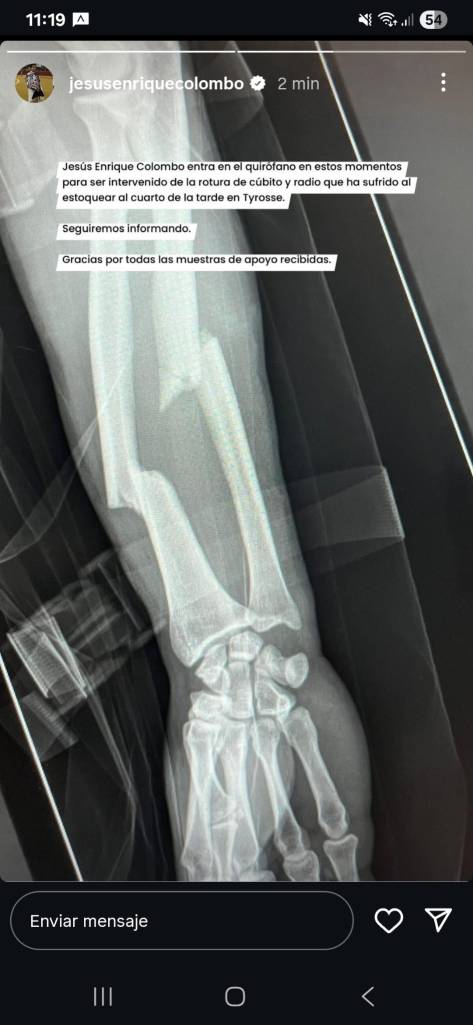

Asi se puede ver lo que ha significado el desafortunado percance de este sabado en la localidad gala de Saint Vincent de Tyrosse. Ya queda, tras operársele ese mismo día en la noche en Dax, una recuperación contra reloj, para de esta manera estar volviendo a los ruedos cuando los tiempos de rehabilitación asi lo indiquen. No es fácil la empresa, pero no imposible para el joven y atlético coleta taribense, quien asume su percance más cuesta arriba, pues siempre las lesiones óseas son las más complicadas y tardías de recuperarse que las mismas cornadas, donde el tejido muscular es más rápida su evolución que las fracturas. Y en Jesús Enrique está la recuperación de dos huesos como son el cubito y radio del antebrazo izquierdo.

Atentos a la evolución que vaya mostrando Jesús Enrique “Colombo” tras su desafortunado percance el pasado sabado en Saint Vincent de Tyrosse. La radiografía muestra el alcance del desafortunado derrite del toro cuando entraba matar. Foto: Cortesía